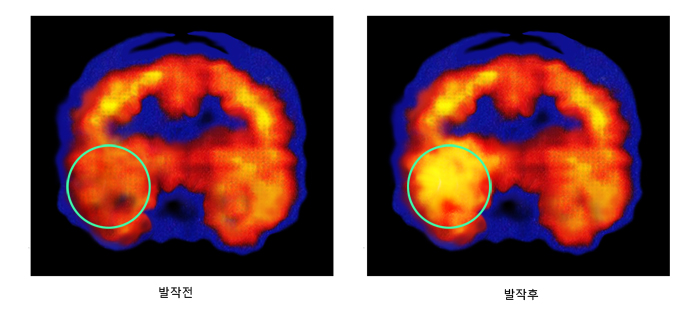

뇌전증은 간헐적으로 발생하는 질환이기 때문에 의사가 환자의 뇌전증을 직접 목격할 가능성은 높지 않다. 따라서 발작 증상 및 관련된 상황에 대해 자세히 병력을 청취하는 것이 필요하다. 발작 양상의 특징에 대한 정보, 과거력을 통한 뇌전증 발생의 위험 인자 규명, 그리고 뇌전증 및 다양한 신경계질환에 대한 가족력 유무 등을 파악하는 데 중점을 둔다. 이를 통해 환자가 호소하는 증상이 뇌전증 발작이 맞는지 확인할 수 있고, 어떤 형태의 뇌전증에 해당하는지 어느 정도 감별할 수 있다. 특히 이 과정에서 종종 뇌전증과 혼동하는 실신에 대한 감별 진단을 할 수 있다. 이 외에 뇌전증 진단에 있어 중요한 검사로는 뇌파검사와 뇌 영상검사가 있다. 뇌전증의 검사 방법은 다음과 같다. 1) 뇌파검사 뇌파검사는 뇌전증의 진단에 있어 가장 중요한 검사이다. 뇌전증은 생리학적으로 대뇌피질세포의 전기적 과활성 상태이다. 따라서 두피에 붙인 뇌파 전극을 통하여 간접적으로 뇌세포의 전기적 활동을 기록하는 것은 뇌전증 여부뿐만 아니라 뇌전증 발작의 시작 위치, 그리고 뇌전증의 분류를 결정하는 데 큰 도움을 준다. 뇌파검사 시 주의해야 할 점이 있는데, 우선 뇌파검사의 민감도가 낮다는 것이다. 일반적으로 뇌전증환자가 뇌파검사를 받을 경우 첫 번째 뇌파 검사에서 뇌전증파가 기록될 확률은 50% 정도에 지나지 않는다. 따라서 뇌전증이 의심되는 환자에서는 3회 정도 뇌파 검사를 반복하는 것이 일반적이다. 또한 여러 차례 검사하더라도 두피에서 기록되는 뇌파검사는 약 20% 정도에서 뇌전증파를 기록하지 못한다고 알려져 있다. 또한 뇌전증의 증상이 전혀 없고 가족력이 없는 정상인의 약 1~2% 정도에서 뇌전증파와 비슷한 모양의 뇌파가 관찰되는 경우가 있다. 특히 소아에서는 이러한 뇌파가 더 자주 관찰되어 판독을 어렵게 한다. 뇌전증의 진단이 확실하지 않거나 뇌전증의 수술적 치료를 위하여 뇌전증 시작 부위를 정확하게 국소화해야 할 필요가 있을 때에는 비디오뇌파검사를 시행하기도 한다. 2) 뇌 영상 검사 뇌전증환자의 일반적인 진단 과정에 있어서 뇌 영상 검사, 특히 뇌 자기공명영상 촬영(뇌 MRI)은 뇌전증의 원인을 규명하는 데 있어 뇌파검사와 함께 가장 중요한 검사이다. MRI로 발견할 수 있는 뇌전증로 인한 병리적 변화는 측두엽뇌전증의 주된 원인인 해마경화, 해면혈관종(cavernous hemangioma), 동정맥기형(arteriovenous malformation) 등의 혈관병변, 뇌연화증(cerebromalacia), 여러 종류의 뇌피질 발달기형(cortical dysplasia), 뇌종양, 기생충, 염증 등이다. MRI로 병리적 변화를 발견할 수 있는 확률은 새로 뇌전증을 진단받은 환자에서는 10~30%이고, 난치성 뇌전증 환자에서는 60% 정도로 알려져 있다. 새로 진단받은 환자에서 MRI 촬영상 병리적 변화가 발견되는 확률이 낮은 이유는, MRI 촬영 목적이 뇌에 어느 정도의 크기 이상의 병리적 변화가 있는 증후성 원인에 의한 뇌전증을 진단하기 위한 것이며, 특발성 및 잠재성 뇌전증의 원인은 발견할 수 없기 때문이다. 모든 부분 뇌전증 및 증상성 뇌전증 환자는 최소한 1회의 MRI를 촬영해야 하지만, 임상적으로 확실한 양성 부분 뇌전증 및 특발성 전신 뇌전증에서는 MRI를 시행하지 않기도 한다. 그러나 일반적으로는 다른 증후성 원인을 배제하기 위한 목적으로 MRI를 시행하는 경우가 많다. 측두엽뇌전증 및 일부 특수한 뇌전증의 경우, 양전자방출 단층촬영(PET)이나 단일광자방출 단층촬영(SPECT)을 시행하여 뇌전증의 원인이 되는 병리적 변화가 생긴 부위에 대한 수술적 절제 여부를 평가하기도 한다. 양전자방출단층촬영은 뇌의 대사 상태를 알아보는 검사이며, 단일광자방출 단층촬영은 뇌혈류를 평가하는 검사이다. 대개 뇌전증의 원인이 되는 병적 변화가 발생한 부위는 발작과 발작 사이에 조직 대사 및 국소 혈류량이 감소되어 있지만, 발작 중에 단일광자방출 단층촬영을 시행할 경우 국소 혈류량이 증가하므로 뇌전증 발작의 원인이 되는 부위를 확인하는 데 큰 도움을 준다. 그러나 상기 두 가지 핵의학 검사는 뇌전증 환자의 일반적인 진단에 있어서는 유용성이 떨어지기 때문에 뇌전증 수술 전 검사나 임상적으로 꼭 필요한 경우에만 시행한다.

우측 측두엽 뇌전증 환자의 단일광자방출 단층촬영